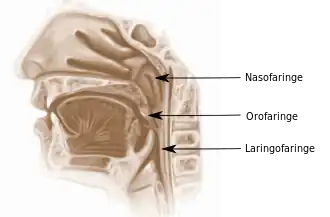

El cavum o nasofaringe constituye la parte superior de la faringe. | ||

El carcinoma de cavum es una tumoración maligna del cavum que es la parte superior de la faringe, también conocida como nasofaringe, epifaringe o rinofaringe. Se encuentra por detrás de las fosas nasales y por delante de la columna vertebral, en esta región desembocan las trompas de Eustaquio.